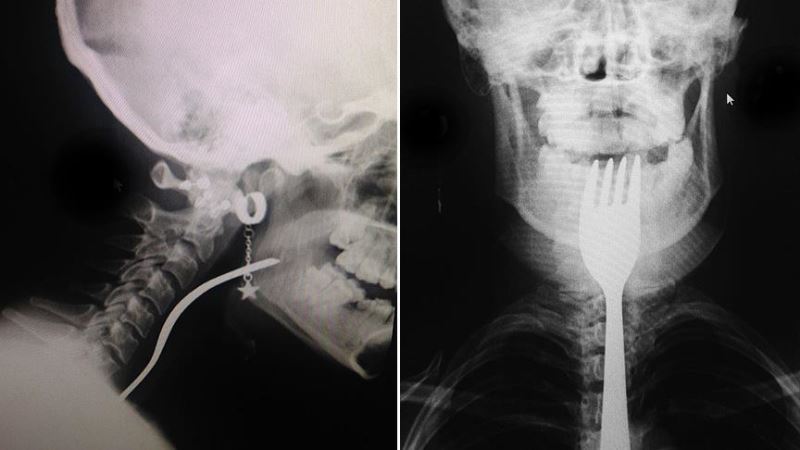

Dikkat: Korkunç olay Bursa'da yaşandı!

Bursa'nın Orhangazi ilçesinde dişini karıştırdığı çatal boğazına girip takılan genç kız, hastaneye kaldırıldı.

Alınan bilgiye göre, Üreğil Mahallesi'nde ailesiyle yaşayan 19 yaşındaki N.A, çatalın ters bölümüyle dişini karıştırmaya başladı. Bu sırada genç kızın boğazına çatal girdi.

Taksici babası İ.H.A. tarafından Orhangazi Devlet Hastanesine kaldırılan N.A, ilk müdahalenin ardından Uludağ Üniversitesi Tıp Fakültesi Hastanesine sevk edildi.

Burada yapılan müdahale sonucu genç kızın boğazına takılan çatal çıkarıldı.